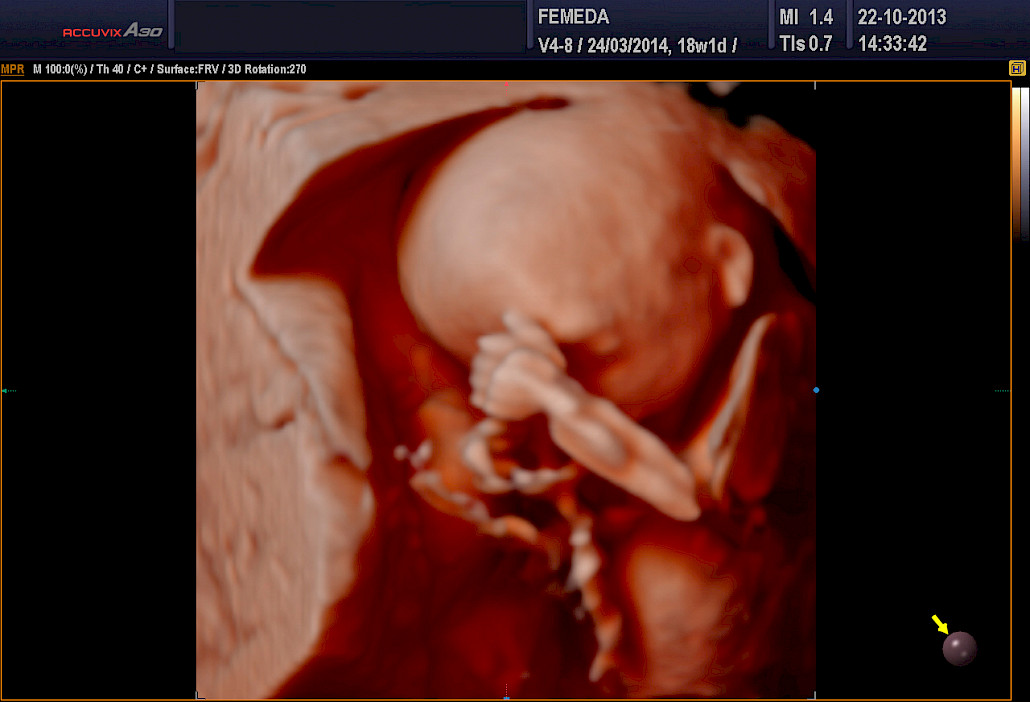

3D ja 4D-tekniikat soveltuvat erityisen hyvin sikiön kasvojen anatomian tutkimiseen. Tutkimuksessa poissuljetaan mahdollinen huulihalkio ja kasvojen profiilissa esiintyvät muut poikkeamat, kuten liian pieni leuka. Samalla selvitetään korvien anatomia ja niiden sijainti. Tekniikan avulla selvitetään raajojen asennot, sekä sormien ja varpaiden lukumäärä ja niiden liikkuvuus. Lisäksi tutkitaan koko selkärangan rakenne ja suljetaan pois poikkeamat, kuten puuttuvat lapa- tai olkaluut.

Kuva Femedan 4D-ultraäänitutkimuksesta